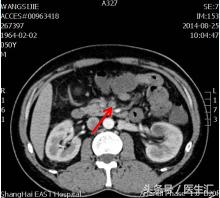

第7天凌晨2:00夜班医生查体全腹部平软,但是上腹部有一点点轻压痛,无反跳痛,麦氏点无压痛,夜班医师给与654-2解痉处理,但是效果还是不满意。所以做了一个中上腹CT平扫示:肠系膜上动、静脉周围渗出性改变,建议增强扫描。第7天早上10:00做中上腹增强CT示:肠系膜上动脉内低密度影,考虑附壁血栓形成,局部管腔重度狭窄。这个时候这个患者的诊断应该来说已经很明确了。于是请了相关科室的医生进行会诊,决定进行经皮选择性肠系膜动脉造影+肠系膜动脉溶栓术。患者溶栓导管行脉冲式注射尿激酶溶栓,患者术后24h出现便血4次,200ml/次。